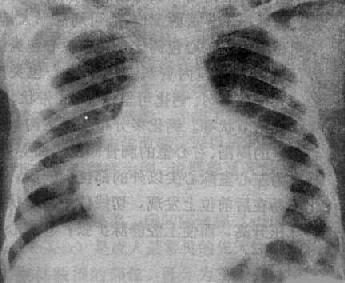

图3-2-16 二尖瓣关闭不全并狭窄

心增大呈二尖瓣型,右心室增大,肺动脉

段突出,左心耳增大,有肺瘀血